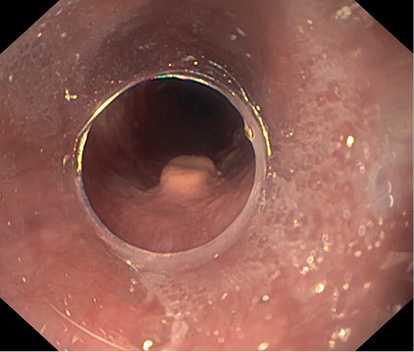

По данным ЭГДС, выполненной при поступлении: на фоне недостаточности кардии и неэрозивного рефлюкс-эзофагита на уровне 33 см от резцов по заднеправой стенке пищевода расположено экзофитное новообразование полиповидной формы размером 8×5 мм белесой окраски, выступающее в просвет на 4—5 мм, симптом шатра отрицательный (рис. 1, 2). Поверхность новообразования гладкая, сосудистый рисунок прослеживается.

Рис. 1. Новообразование по заднеправой стенке пищевода. Фото авторов.

Рис. 2. Новообразование по заднеправой стенке пищевода. Фото авторов.